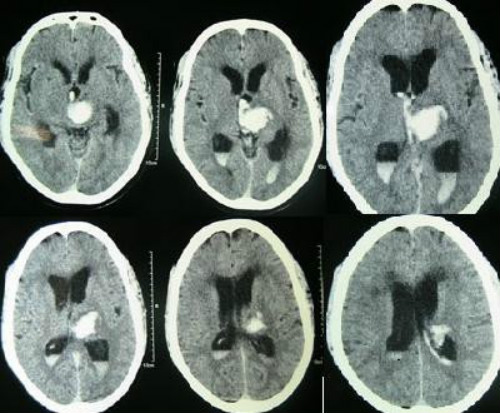

Change in ambient temperature of the past 24 hours – specifically, decrease in temperature – correlates with an increased risk of intracranial hemorrhage (ICH), according to a study published recently in the International Journal of Environmental Research and Public Health. The study, “Ambient Temperature and Stroke Occurrence: A Systematic Review and Meta-Analysis,” found that that lower mean ambient temperature was significantly associated with ICH risk (Figure 1).

with associated hydrocephalus and blood in the third and both lateral ventricles.

(Sources: Wikipedia/By Yadav YR, Mukerji G, Shenoy R, Basoor A, Jain G, Nelson A - Yadav YR, Mukerji G, Shenoy R, Basoor A, Jain G, Nelson A (2007). "Endoscopic management of hypertensive intraventricular haemorrhage with obstructive hydrocephalus". BMC Neurol./Creative Commons.)

Intracerebral hemorrhage (Figure 2) represents approximately 10% to 15% (10-30/100,000 population) of all strokes. About 2 million of the 15 million strokes worldwide are intracerebral hemorrhages. Men are more likely to suffer an intracerebral hemorrhage than women.